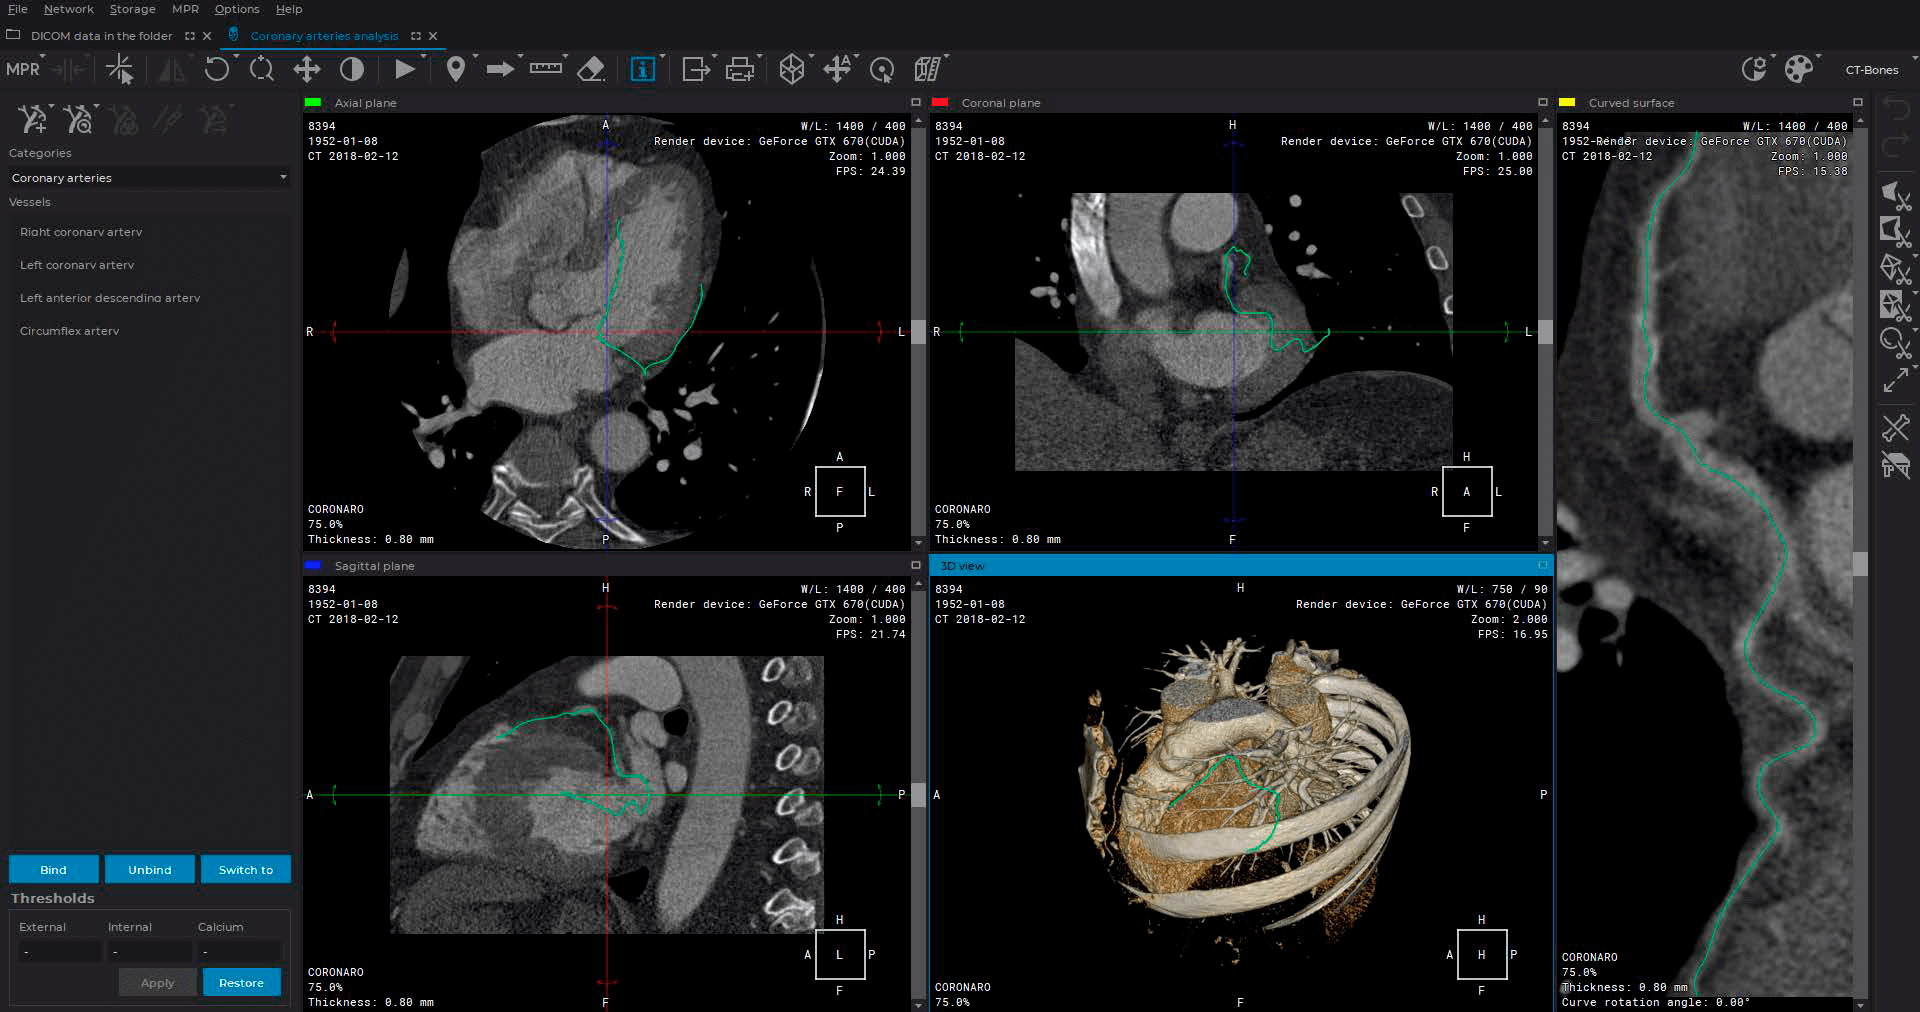

Advanced capabilities for working with 3D reconstructions

Advanced multiplanar reconstruction capabilities